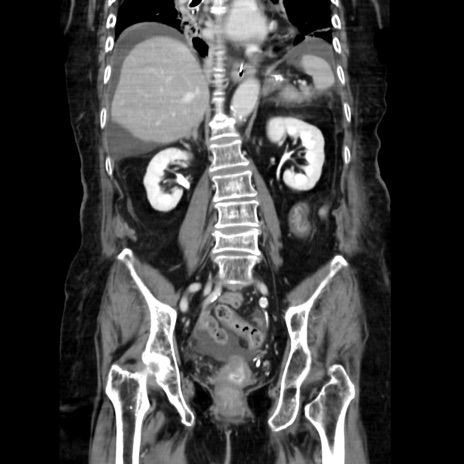

症例40(冠状断像)

【症例】90歳代女性

【主訴】腹痛・嘔吐

【現病歴】 食欲低下、嘔吐があり昨日他院受診。肺炎と診断され入院となる。入院後より腹部全体に圧痛あり。胃管留置され経過みていたが、症状持続するため、

当院転院となる。

【既往歴】胸椎圧迫骨折、胆石症

【身体所見】腹部:中央に激痛あり、圧痛あり、反跳痛不明

【データ】WBC 17100、CRP 18.82

冠状断像